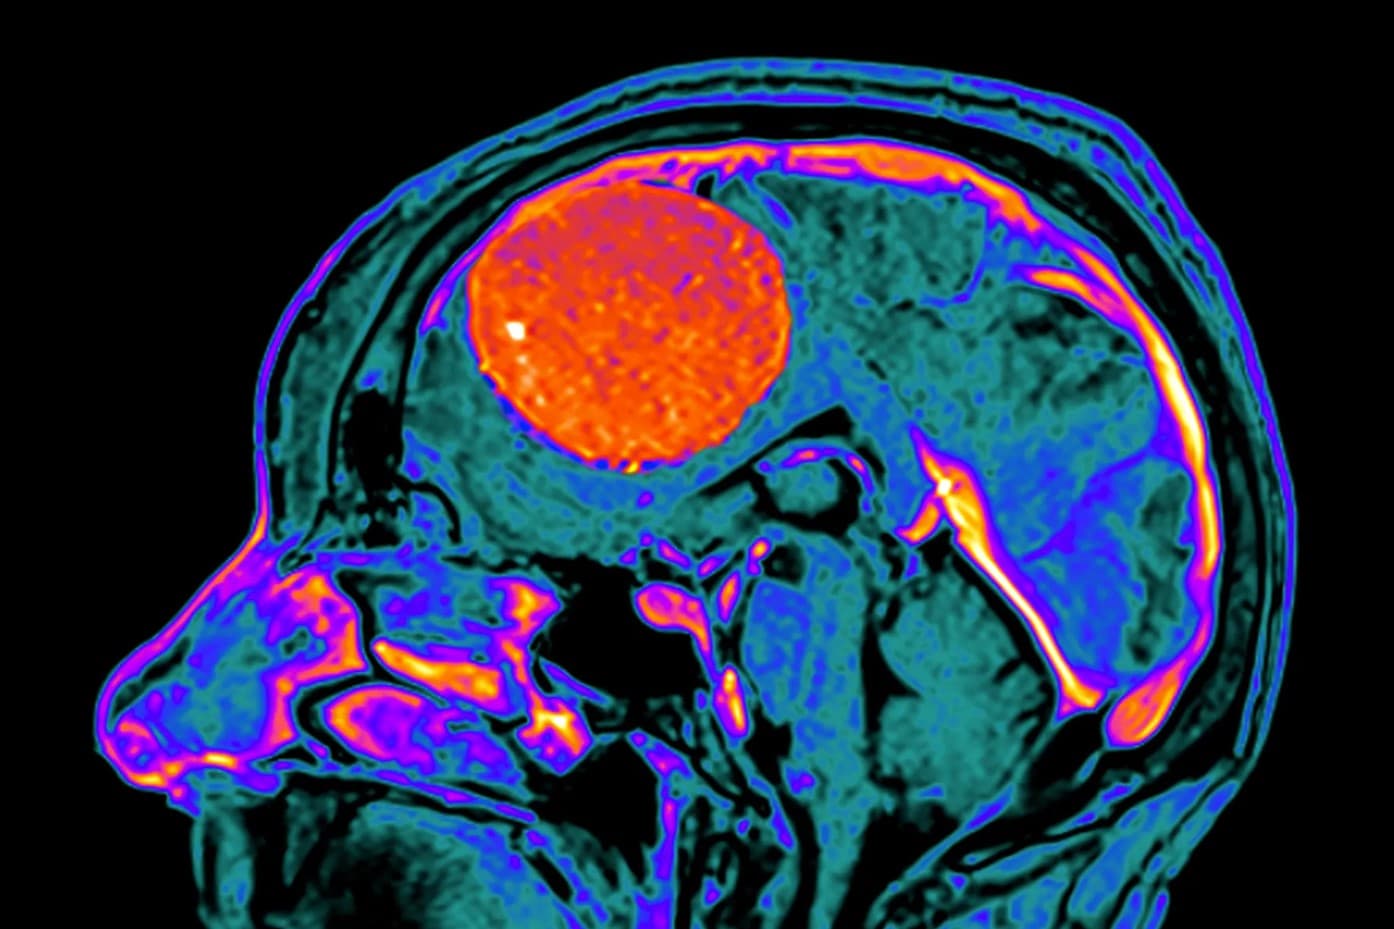

6. Chẩn đoán u màng não

U màng não hiếm khi được phát hiện sớm trước khi xuất hiện triệu chứng.

Nếu có dấu hiệu nghi ngờ khối u, bác sĩ có thể chỉ định chụp MRI và/hoặc CT scan để xác định vị trí và kích thước của khối u.

Trong một số trường hợp, bác sĩ có thể tiến hành sinh thiết. Phẫu thuật viên sẽ lấy một phần hoặc toàn bộ khối u để kiểm tra xem đó là khối u lành tính hay ác tính.